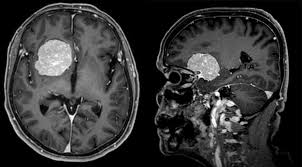

Klinik Und Poliklinik Fuer Neurochirurgie Meningeome